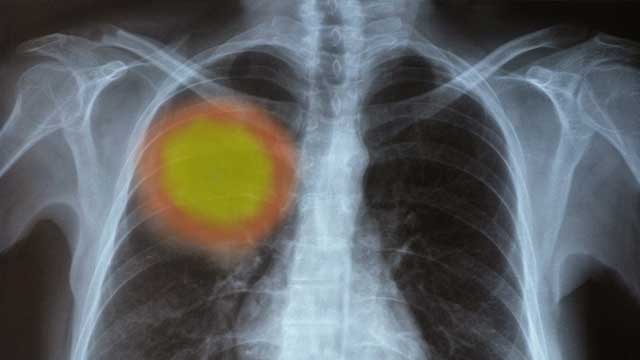

"코로나19에 감염이 된 후에는 폐 섬유화(폐가 굳는 현상)로 영구 장애를 안고 살아야 한다"라는 내용이 2020년 2월 초부터 인터넷 카페와 SNS에서 자주 찾아볼 수 있었습니다.

중국 베이징의 수도의과 대학병원 연구팀이 1월 15일에 작성한 `코로나바이러스 감염증 보고서' 내용을 다룬 리포트입니다. 당시 기준으로, 대부분의 환자는 양호했지만 소수의 환자에게서 사망까지 이르는 중증 폐렴 증상이 나타났고, 그런 경우 정상인의 폐 CT와 달리 환자의 폐가 하얗게 변했다는 내용이 담겼습니다.